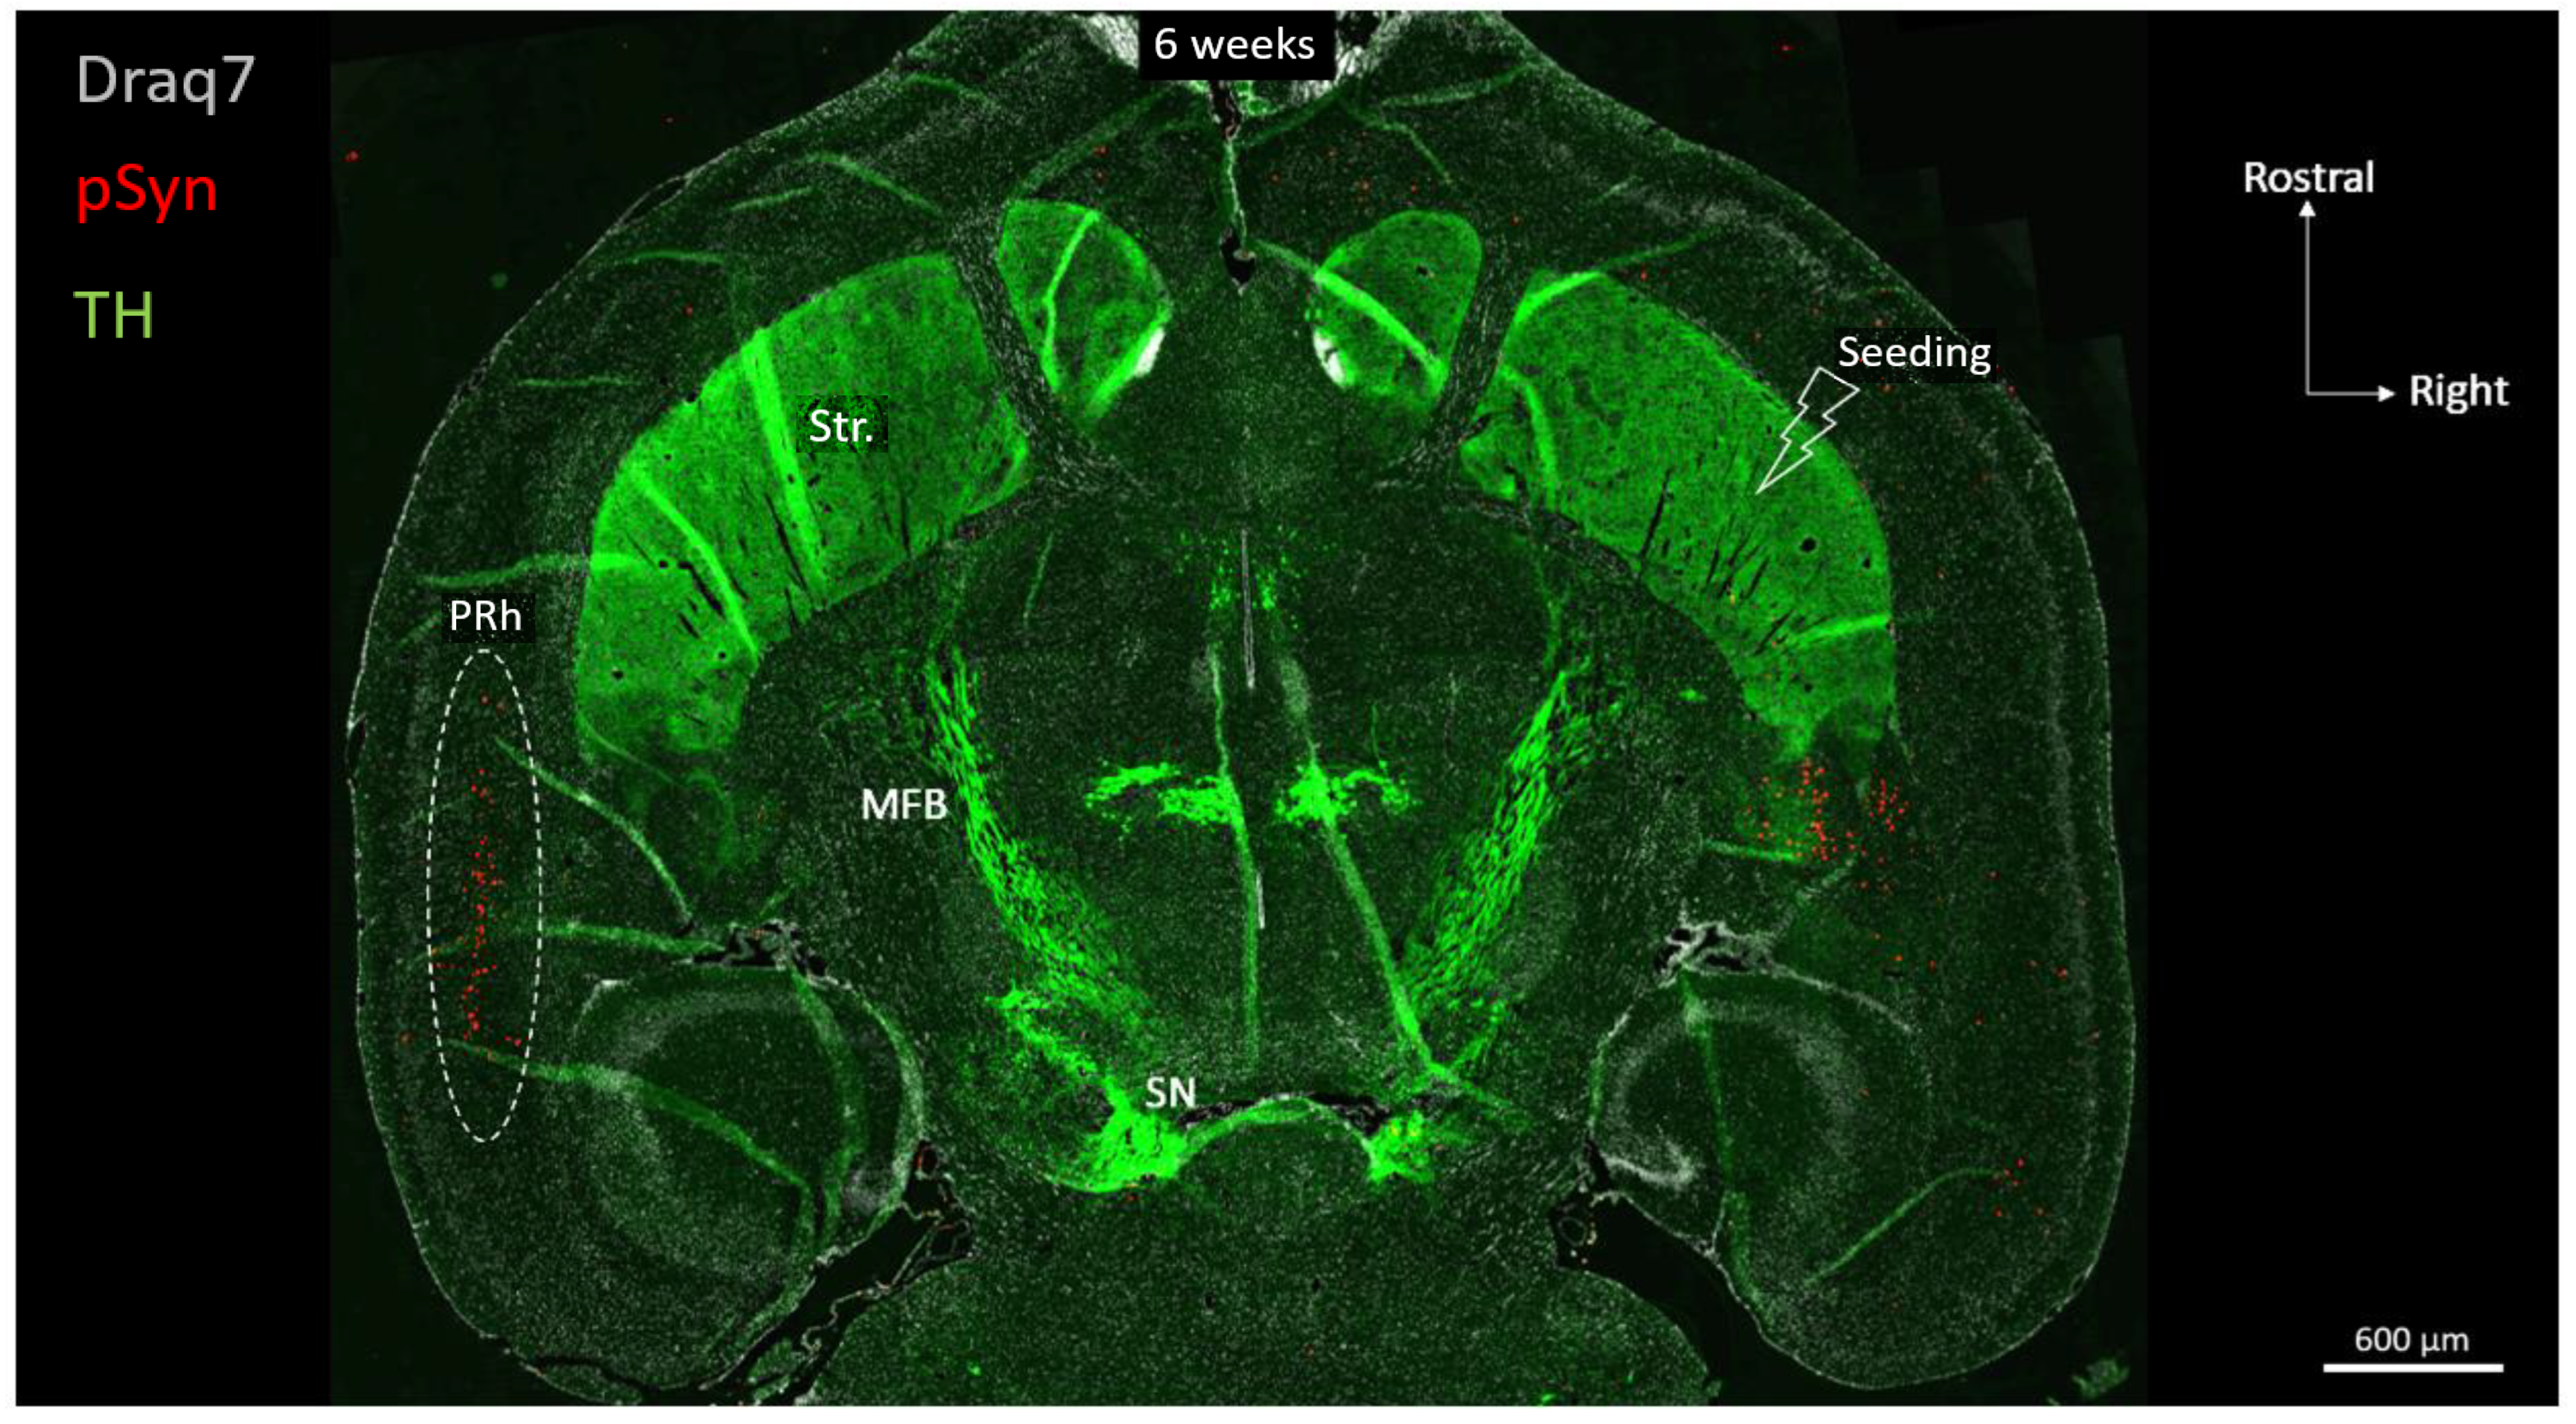

Figure 3 shows a full brain semi-horizontal paraffin section of such an animal in which the full span of the nigrostriatal tract can be seen in green (anti-Tyrosine hydroxylase antibody, TH).

Figure 3.

Horizontal topography of Tyrosine Hydroxylase (green, TH), α-Syn pathology (red, pSyn), and cell nuclei (white, Draq7) 6 weeks after seeding with 1B fibrils into the right striatum of a wild-type mouse (10 µm full brain section). SN: Substantia nigra; MFB: median forebrain bundle; Str.: ventral striatum (nucleus accumbens core and shell); PRh: perirhinal cortex.

The level of the section is ventral enough to encompass the ventral striatum (nucleus accumbens core and shell), the anterior commissure limbs, the median forebrain bundle, and the ventral part of the substantia nigra. The pSyn-positive aggregates (pSyn#64 antibody) appear in red, and with this level of zoom one can clearly perceive the invasion of the ipsilateral amygdala and entorhinal cortex, but also and most strikingly, of the median layer of the contralateral perirhinal cortex (layer V). The quick and massive spread of the α-Syn pathology to contralateral somas of cortical neurons is due to the coincidence of 2 constraints: an anatomical one, and a functional one.